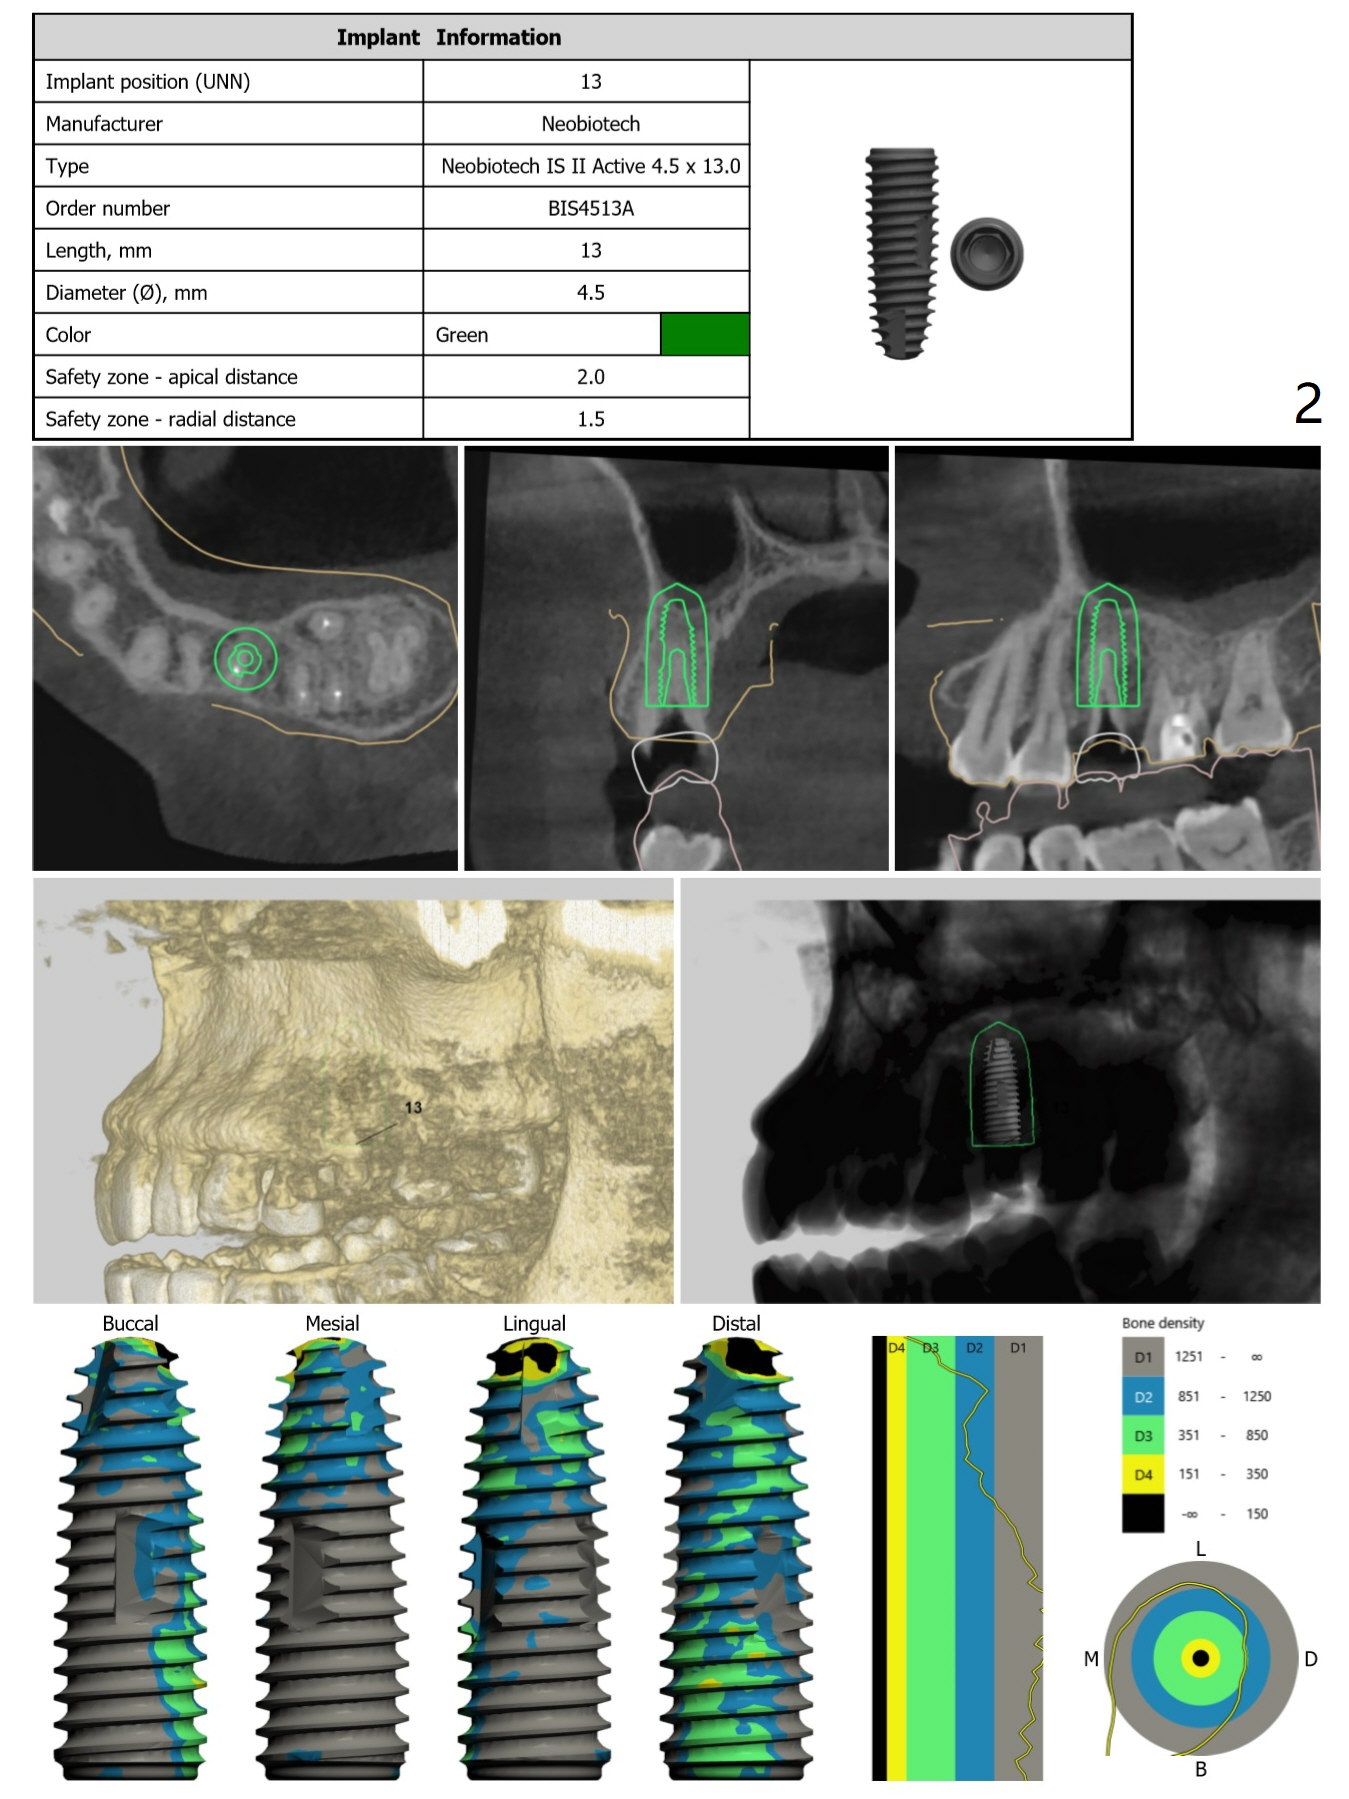

Underprep in Depth for Sinus Lift

After #13 implant placement, remove DO caries at #14 for composite and splinted provisional. Consider taking PA after 2.2 mm drill to depth because of the curved root of #12. Placee IBS implant with IS driver.